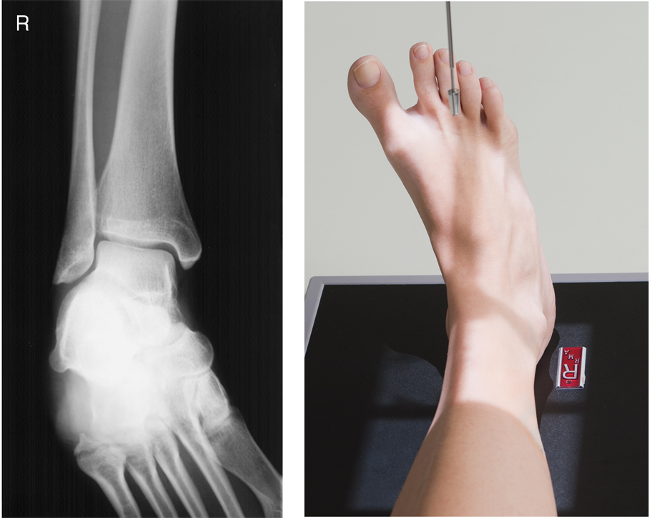

AP Ankle

• IR 10x12 IR landscape, 40 SID

• Pt supine, legs fully extended. Center ankle joint to CR and long axis of IR. Dorsiflexion. Ensure lower leg is not rotated. Intermalleolar line should not be parallel

• CR enters perpendicular to midpoint between malleoli. Collimate to lateral ST margins and include prox. MT and distal tib/fib